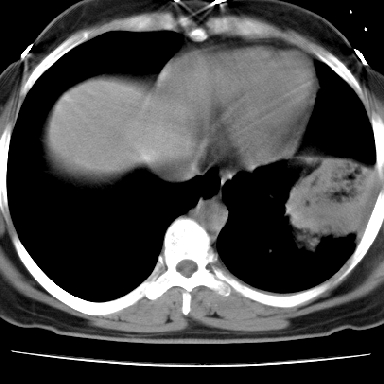

f 37 咳嗽1周,咯血1次,无浓痰,无明显发热

左下肺肿块影,内可以见小泡征,并见厚壁空洞形成,洞内缘凹凸不平,可见壁结节。靠近胸膜侧可见胸膜凹陷征。左侧胸腔内可见少量低密度积液影。右肺可见两处高致密的小结节影。

考虑:左下肺周围型肺癌伴右肺转移

左下肺肿块影,内可以见小泡征,并见厚壁空洞形成,洞内缘凹凸不平,可见壁结节。靠近胸膜侧可见胸膜凹陷征。左侧胸腔内可见少量低密度积液影。双肺可见多发性小结节影。

考虑:左下肺癌性空洞伴两肺转移